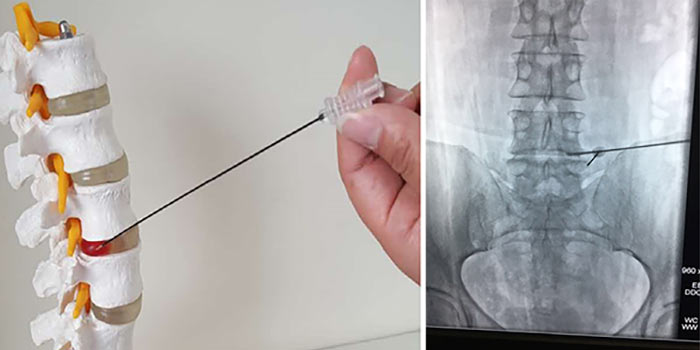

Диагноз подтверждают с помощью биопсии. Врач получает фрагмент опухолевой ткани и отправляет в лабораторию для цитологического, гистологического исследования, молекулярно-генетических анализов. Материал для биопсии может быть получен разными путями:

- Чаще всего проводят пункционную чрескожную биопсию с помощью иглы, которую вводят под контролем рентгена.

- Реже часть опухоли или всю ее целиком удаляют хирургически. Такая биопсия называется соответственно инцизионной и эксцизионной.